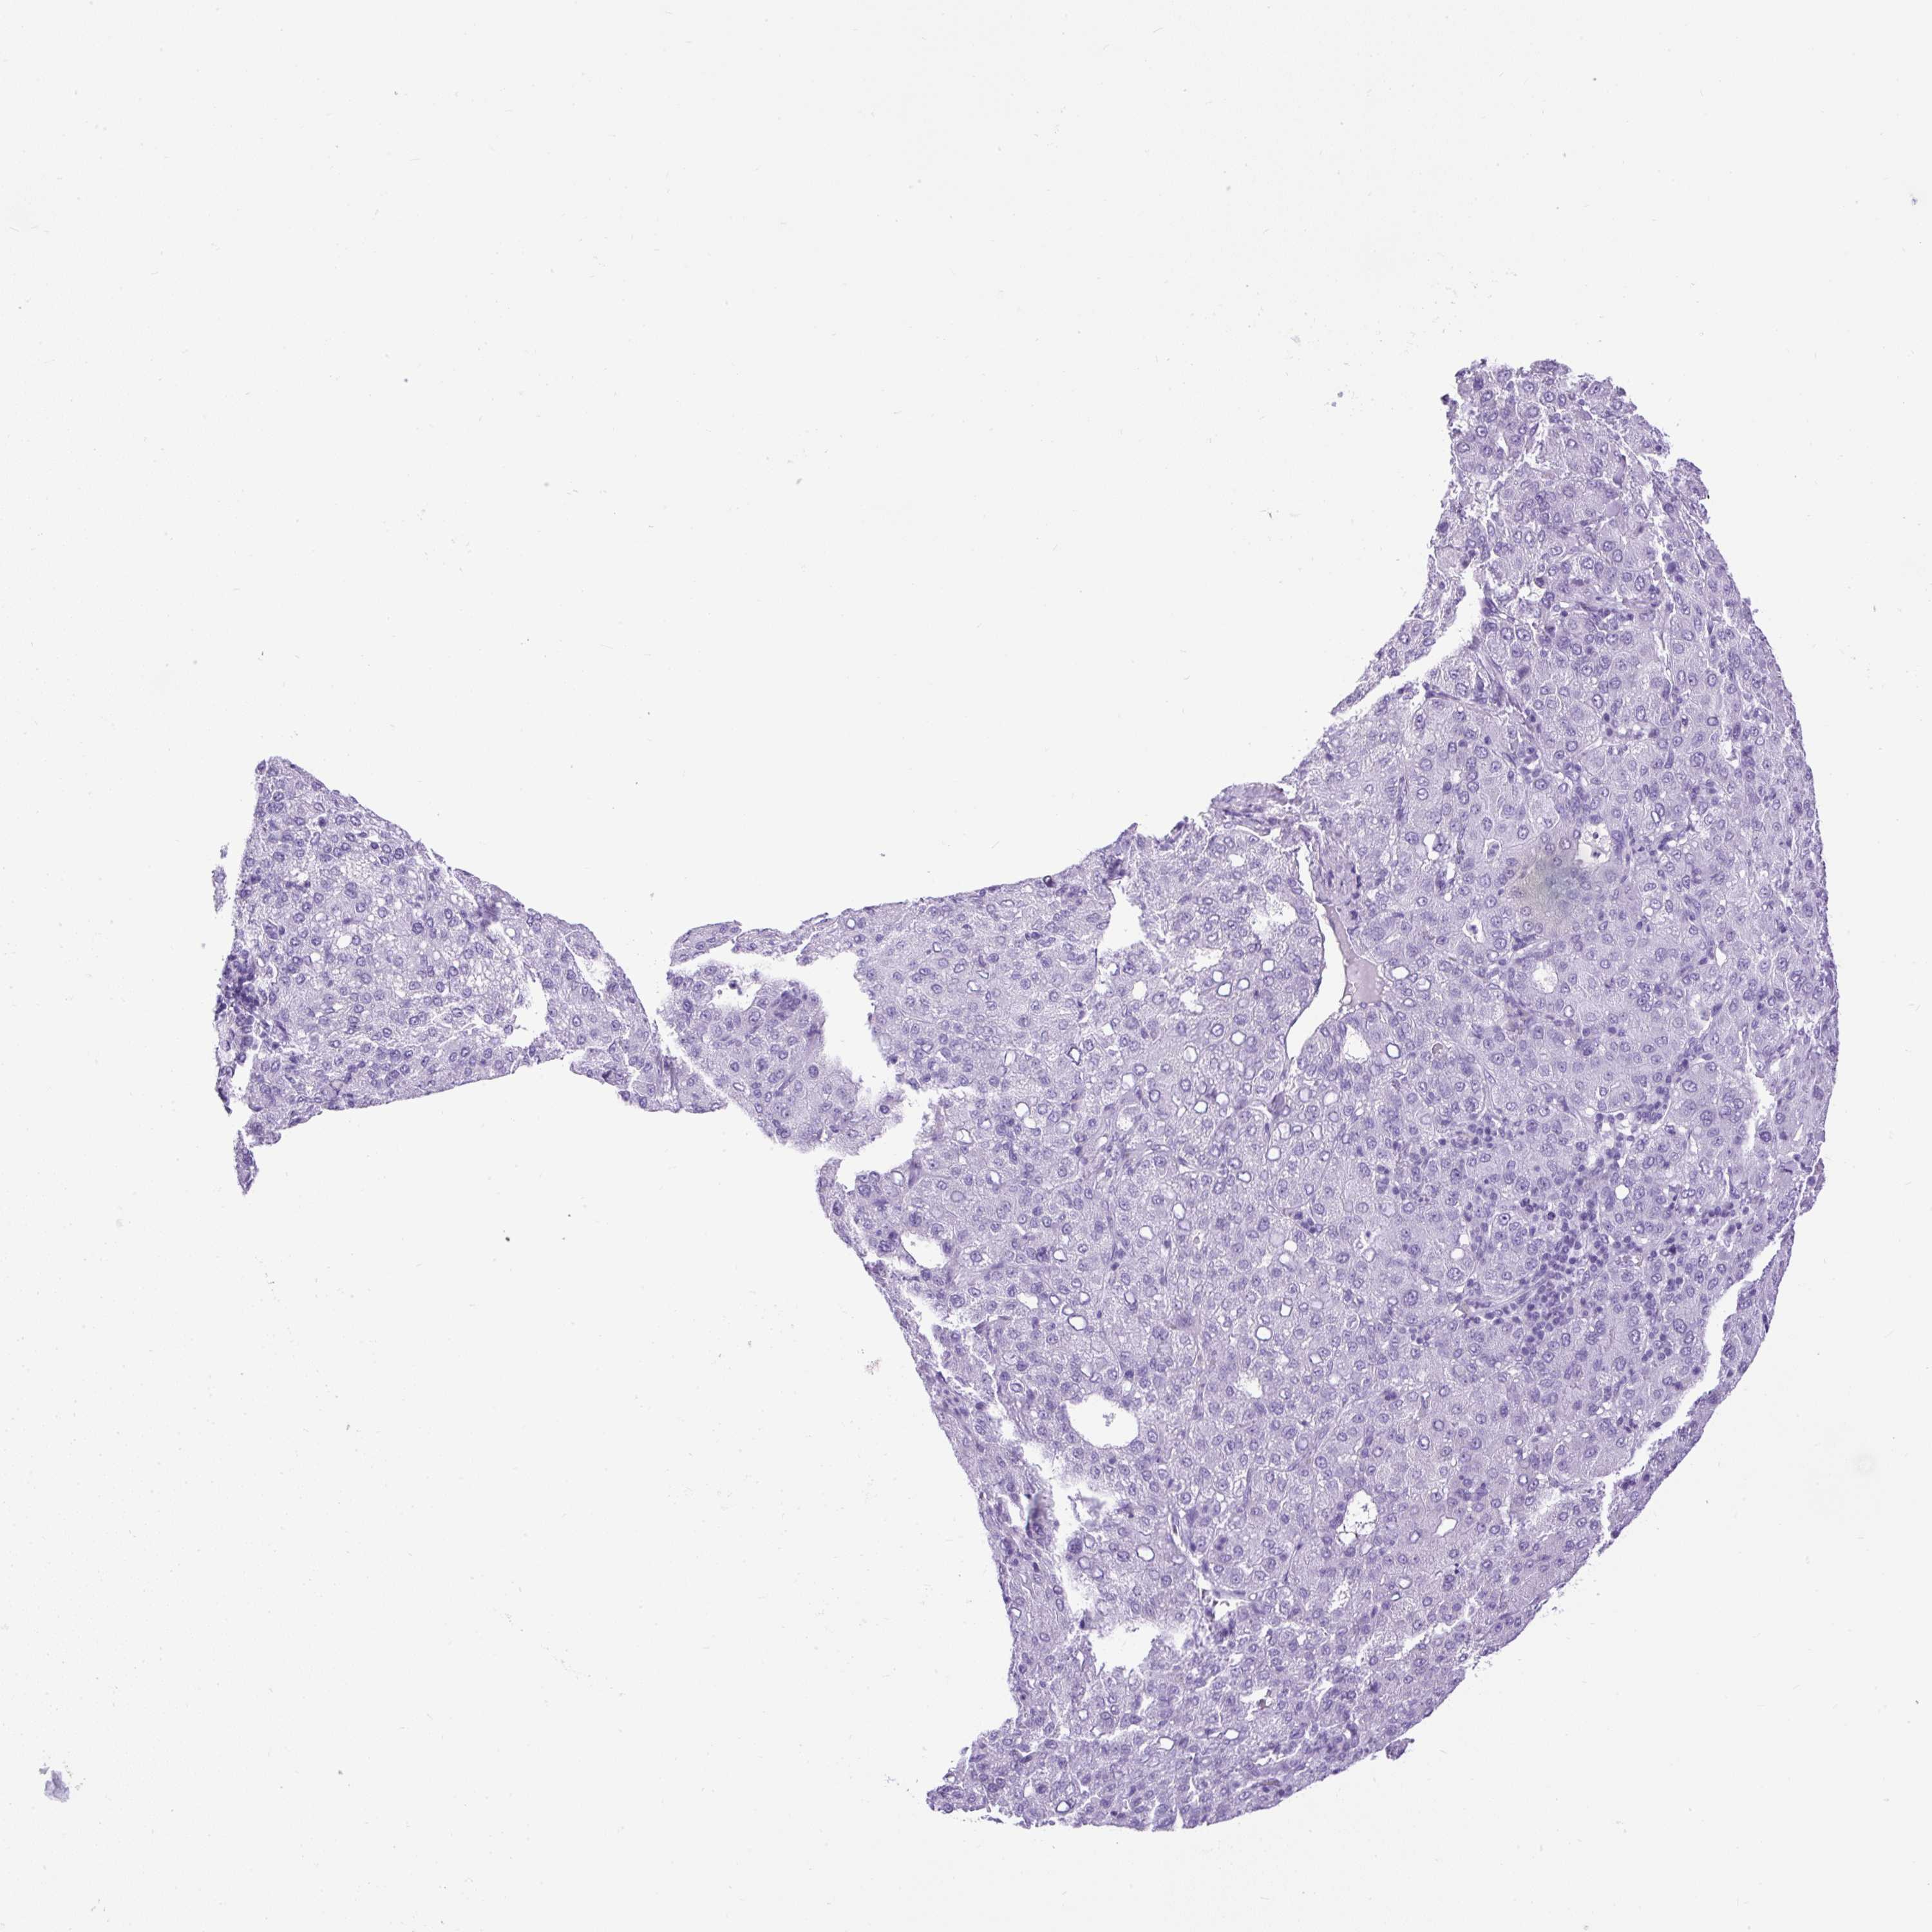

LIVER CANCER - Protein expressioni

A mouse-over function shows sample information and annotation data. Click on an image to view it in a full screen mode. Samples can be filtered based on level of antibody staining by selecting one or several of the following categories: high, medium, low and not detected. The assay and annotation is described here.

Note that samples used for immunohistochemistry by the Human Protein Atlas do not correspond to samples in the TCGA dataset.

Antibody stainingi

Antibody staining in the annotated cell types in the current human tissue is reported as not detected, low, medium, or high, based on conventional immunohistochemistry profiling in selected tissues. This score is based on the combination of the staining intensity and fraction of stained cells.

Each image is clickable and will lead to virtual microscopy that enables deeper exploration of all samples and also displays staining intensity scores, fraction scores and subcellular localization as well as patient and tissue information for each sample.

Antibody HPA008023

Antibody HPA052701

Staining

High

Medium

Low

Not detected

Intensity

Strong

Moderate

Weak

Negative

Quantity

>75%

75%-25%

<25%

None

Location

Nuclear

Cytoplasmic/membranous

Cytoplasmic/membranous,nuclear

Cholangiocarcinoma

Carcinoma, Hepatocellular, NOS